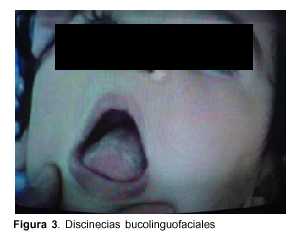

Lactante de 1 año, raza blanca, sexo femenino, con antecedentes familiares de padres consanguíneos (parientes tres grados aparte). Producto de primera gestación, embarazo normal, parto de término. Peso al nacer 4.500 g, longitud 53 cm, perímetro cefálico 35 cm. Test de Apgar 6/8. Buen crecimiento y desarrollo (figura 2). Comienza su enfermedad dos días después de una enfermedad diarreica aguda, caracterizada por trastorno de conciencia, crisis convulsiva generalizada tónica y movimientos anormales bucolinguofaciales y de las extremidades. El examen físico al ingreso mostró: perímetro cefálico 47 cm, peso 10.200 g, longitud 80 cm. Sin alteraciones morfológicas, vigil, hiporreactiva, movimientos anormales espontáneos caracterizados por discinecias bucolinguofaciales (figura 3) y movimientos distónicos a predominio distal en hemicuerpo izquierdo (figura 4). Hipotonía axial severa, sin sostén cefálico ni sedestación e hipertonía espástica, hiperreflexia, clonus y Babinski bilateral a predominio derecha.

Nuestra paciente se presenta con la forma clásica de AGI que se inicia entre los 2 y los 37 meses de edad con síntomas agudos(6). Consiste en la aparición brusca en el curso de una infección banal, inmunización, ayuno prolongado u otra situación hipercatabólica, de síntomas neurológicos que involucran principalmente el sistema extrapiramidal, siendo el desarrollo madurativo generalmente normal hasta ese momento(3,5,6). La paciente presentó, en forma brusca, hipotonía severa, movimientos distónicos principalmente bucolinguofaciales, irritabilidad, convulsiones y alteraciones piramidales sin acidosis metabólica. La enfermedad fue interpretada inicialmente como una encefalitis. Pasado el episodio agudo se produce una mejoría incompleta persistiendo la distonía y la coreoatetosis(12,13), si bien hay descripciones de algún caso con remisión completa luego del episodio agudo(6). No es infrecuente la disfunción hepática durante la descompensación(3), como fue detectado en nuestro caso con aumento de GOT y GPT. Otra forma de presentación aguda menos frecuente de la AGI es la llamada crisis metabólica con hipoglicemia hipocetósica y acidosis metabólica que progresa como si se tratase de un síndrome de Reye y que tendría como un importante factor causal deficiencia de carnitina (c). En la AGI se produce una deficiencia secundaria de carnitina, con relación esterificada/libre frecuentemente elevada(14). En nuestro caso, al momento de la evaluación, había un discreto descenso de carnitina total con leve disminución del porcentaje de la libre.